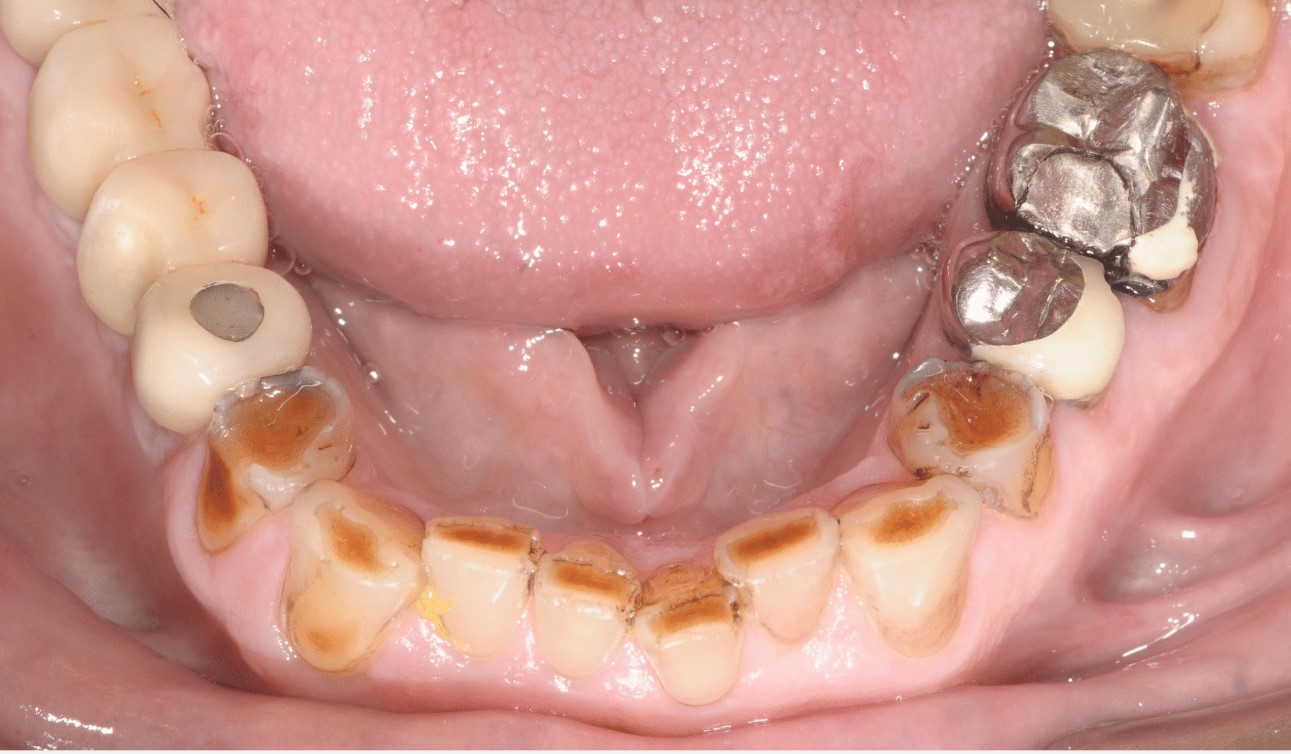

Attrition and wear facets evident in a bruxist patient

Diagnosis of bruxism can come about through features found extra- and intra-orally. Extra-orally, the patient may have hypertrophic masticatory muscles. Intra-orally, attrition and wear facets on teeth due to the lateral and excursive movements may be evident. This may further be associated with symptoms such as tooth sensitivity, jaw tenderness or muscle fatigue. Tooth fractures can be a severe consequence.